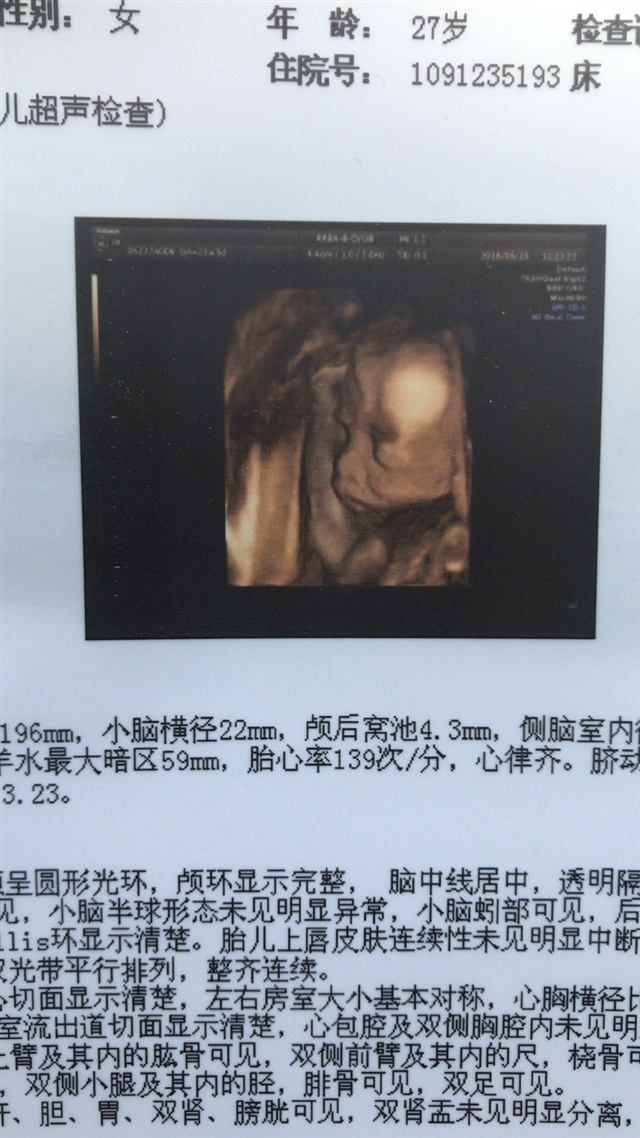

孕18周+5天

有点像男宝

男宝吧